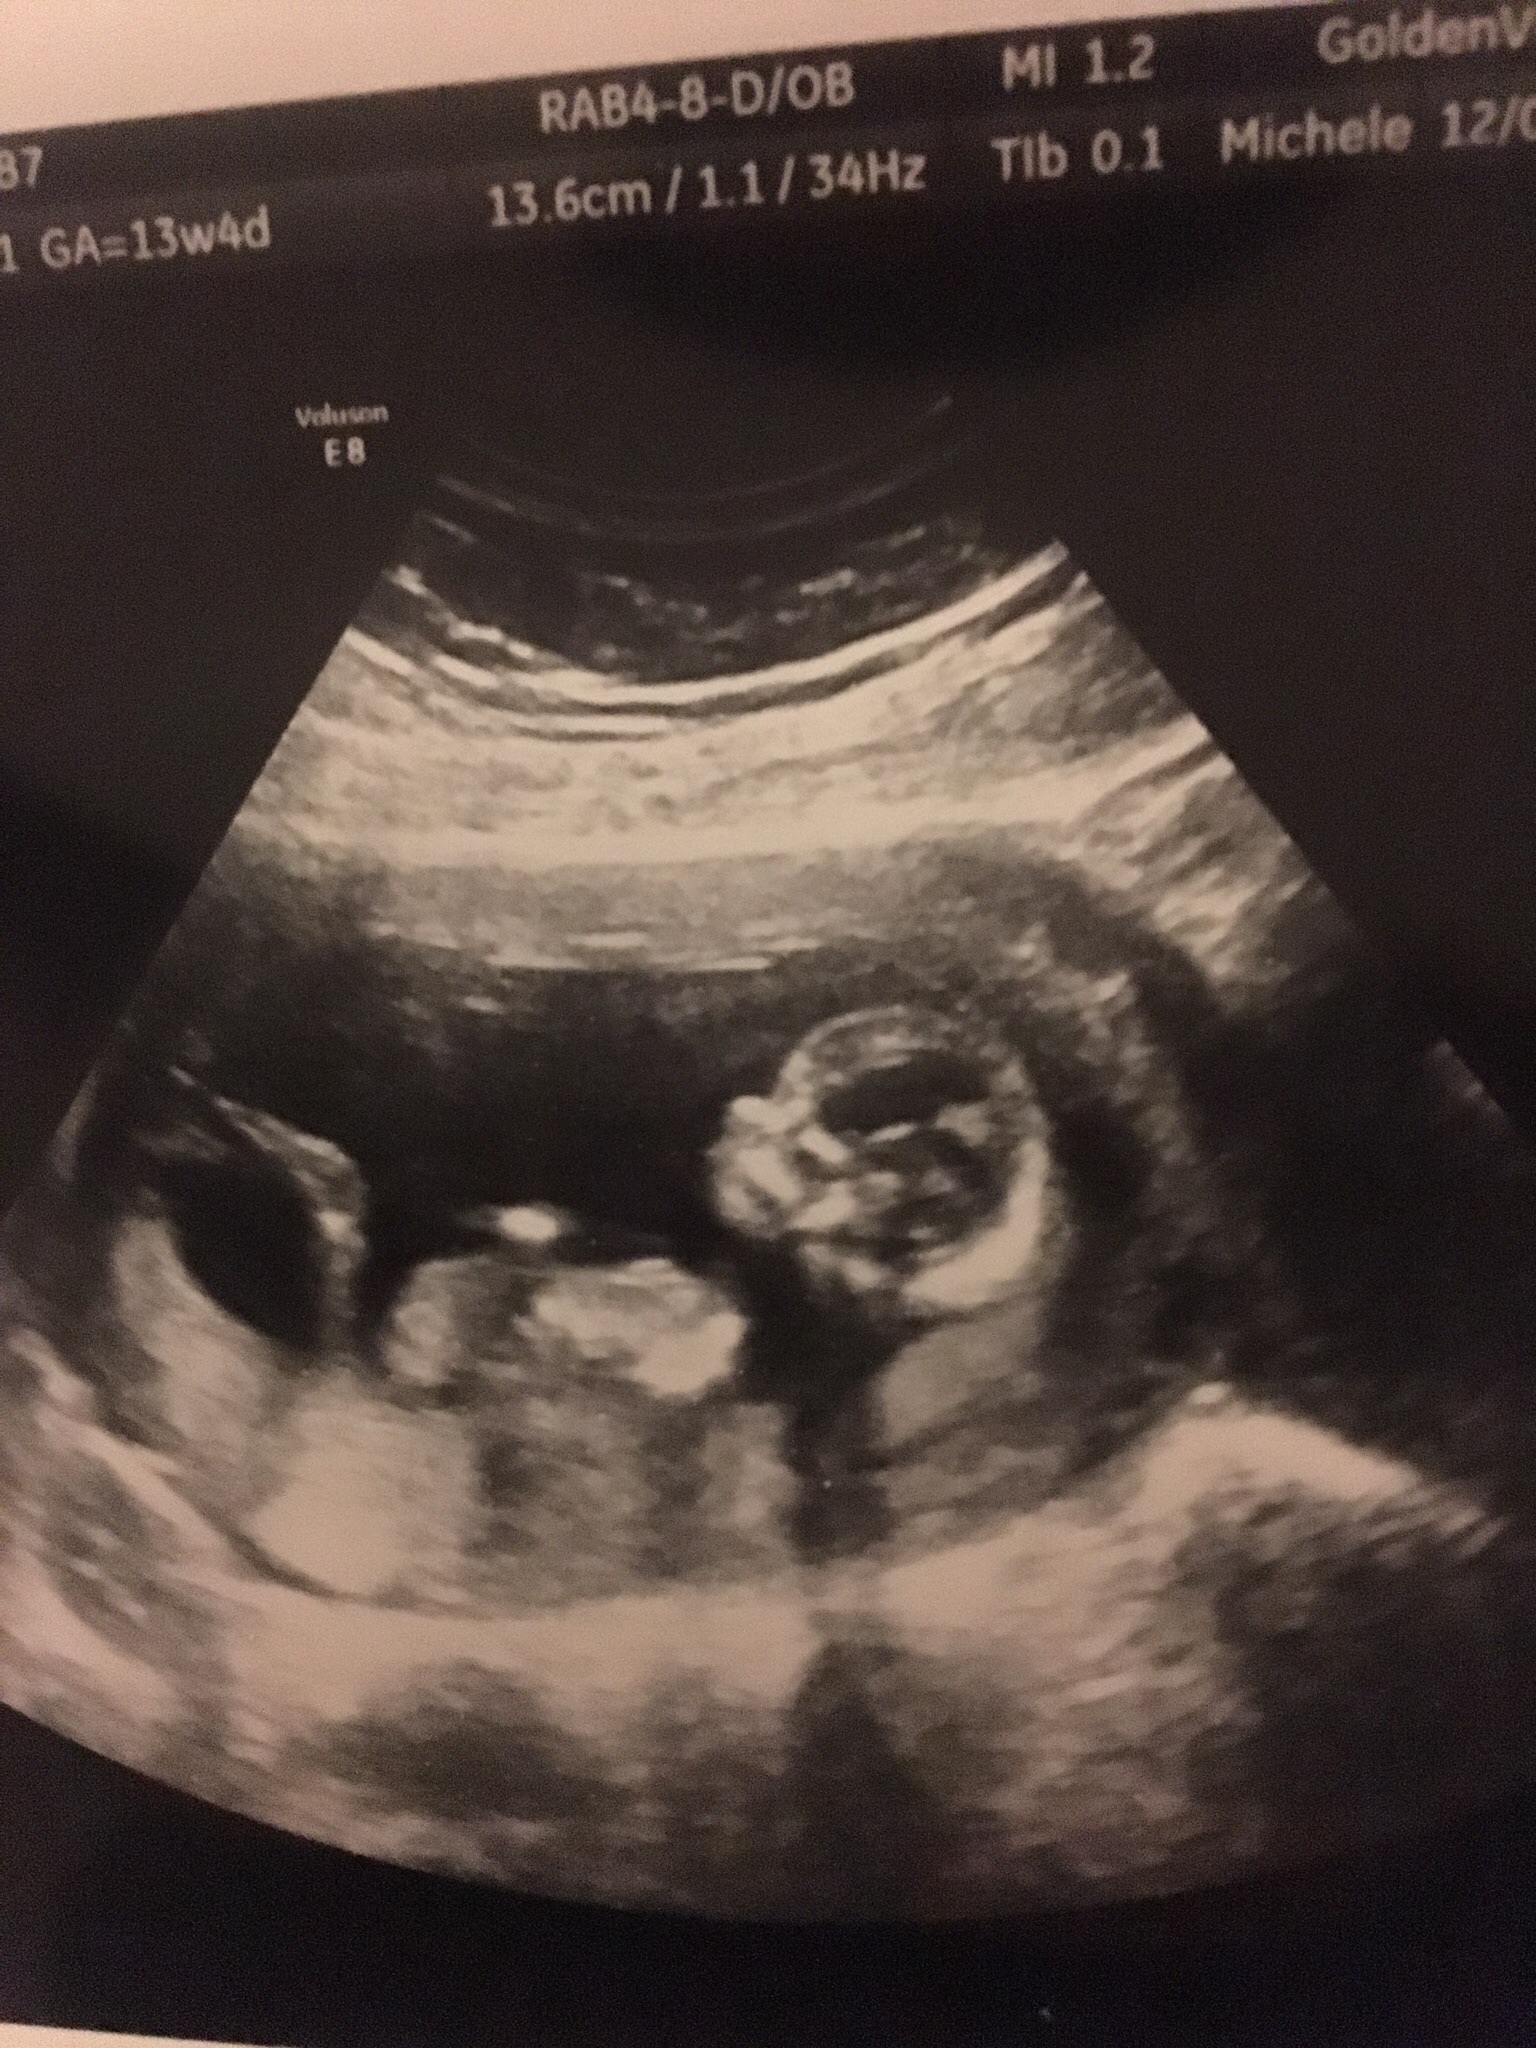

Had my NT scan today. Such a huge difference from my 7 week ultrasound. It actually had arms and legs this time!!

12w 1d